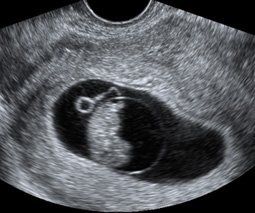

Erken Gebelik Taraması

- Erken / yaşayabilir gebeliğin doğrulanması

- Gebelik kesesinin ve Tepe Kıç Uzunluğunun (CRL) ölçümü (mümkünse)

- Kalp atışı tespiti. (Hamilelik 6 haftadan fazla ise.

- 6 ila 10 hafta arasında.